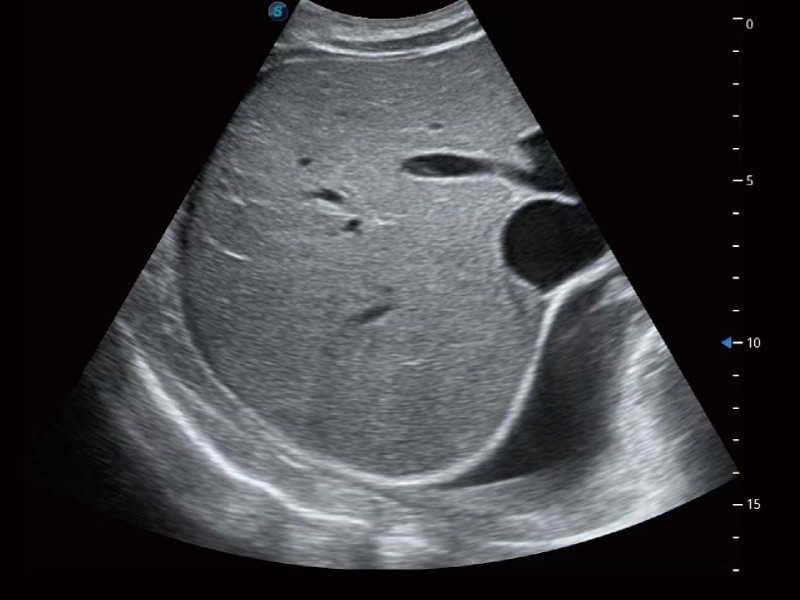

腹部应用